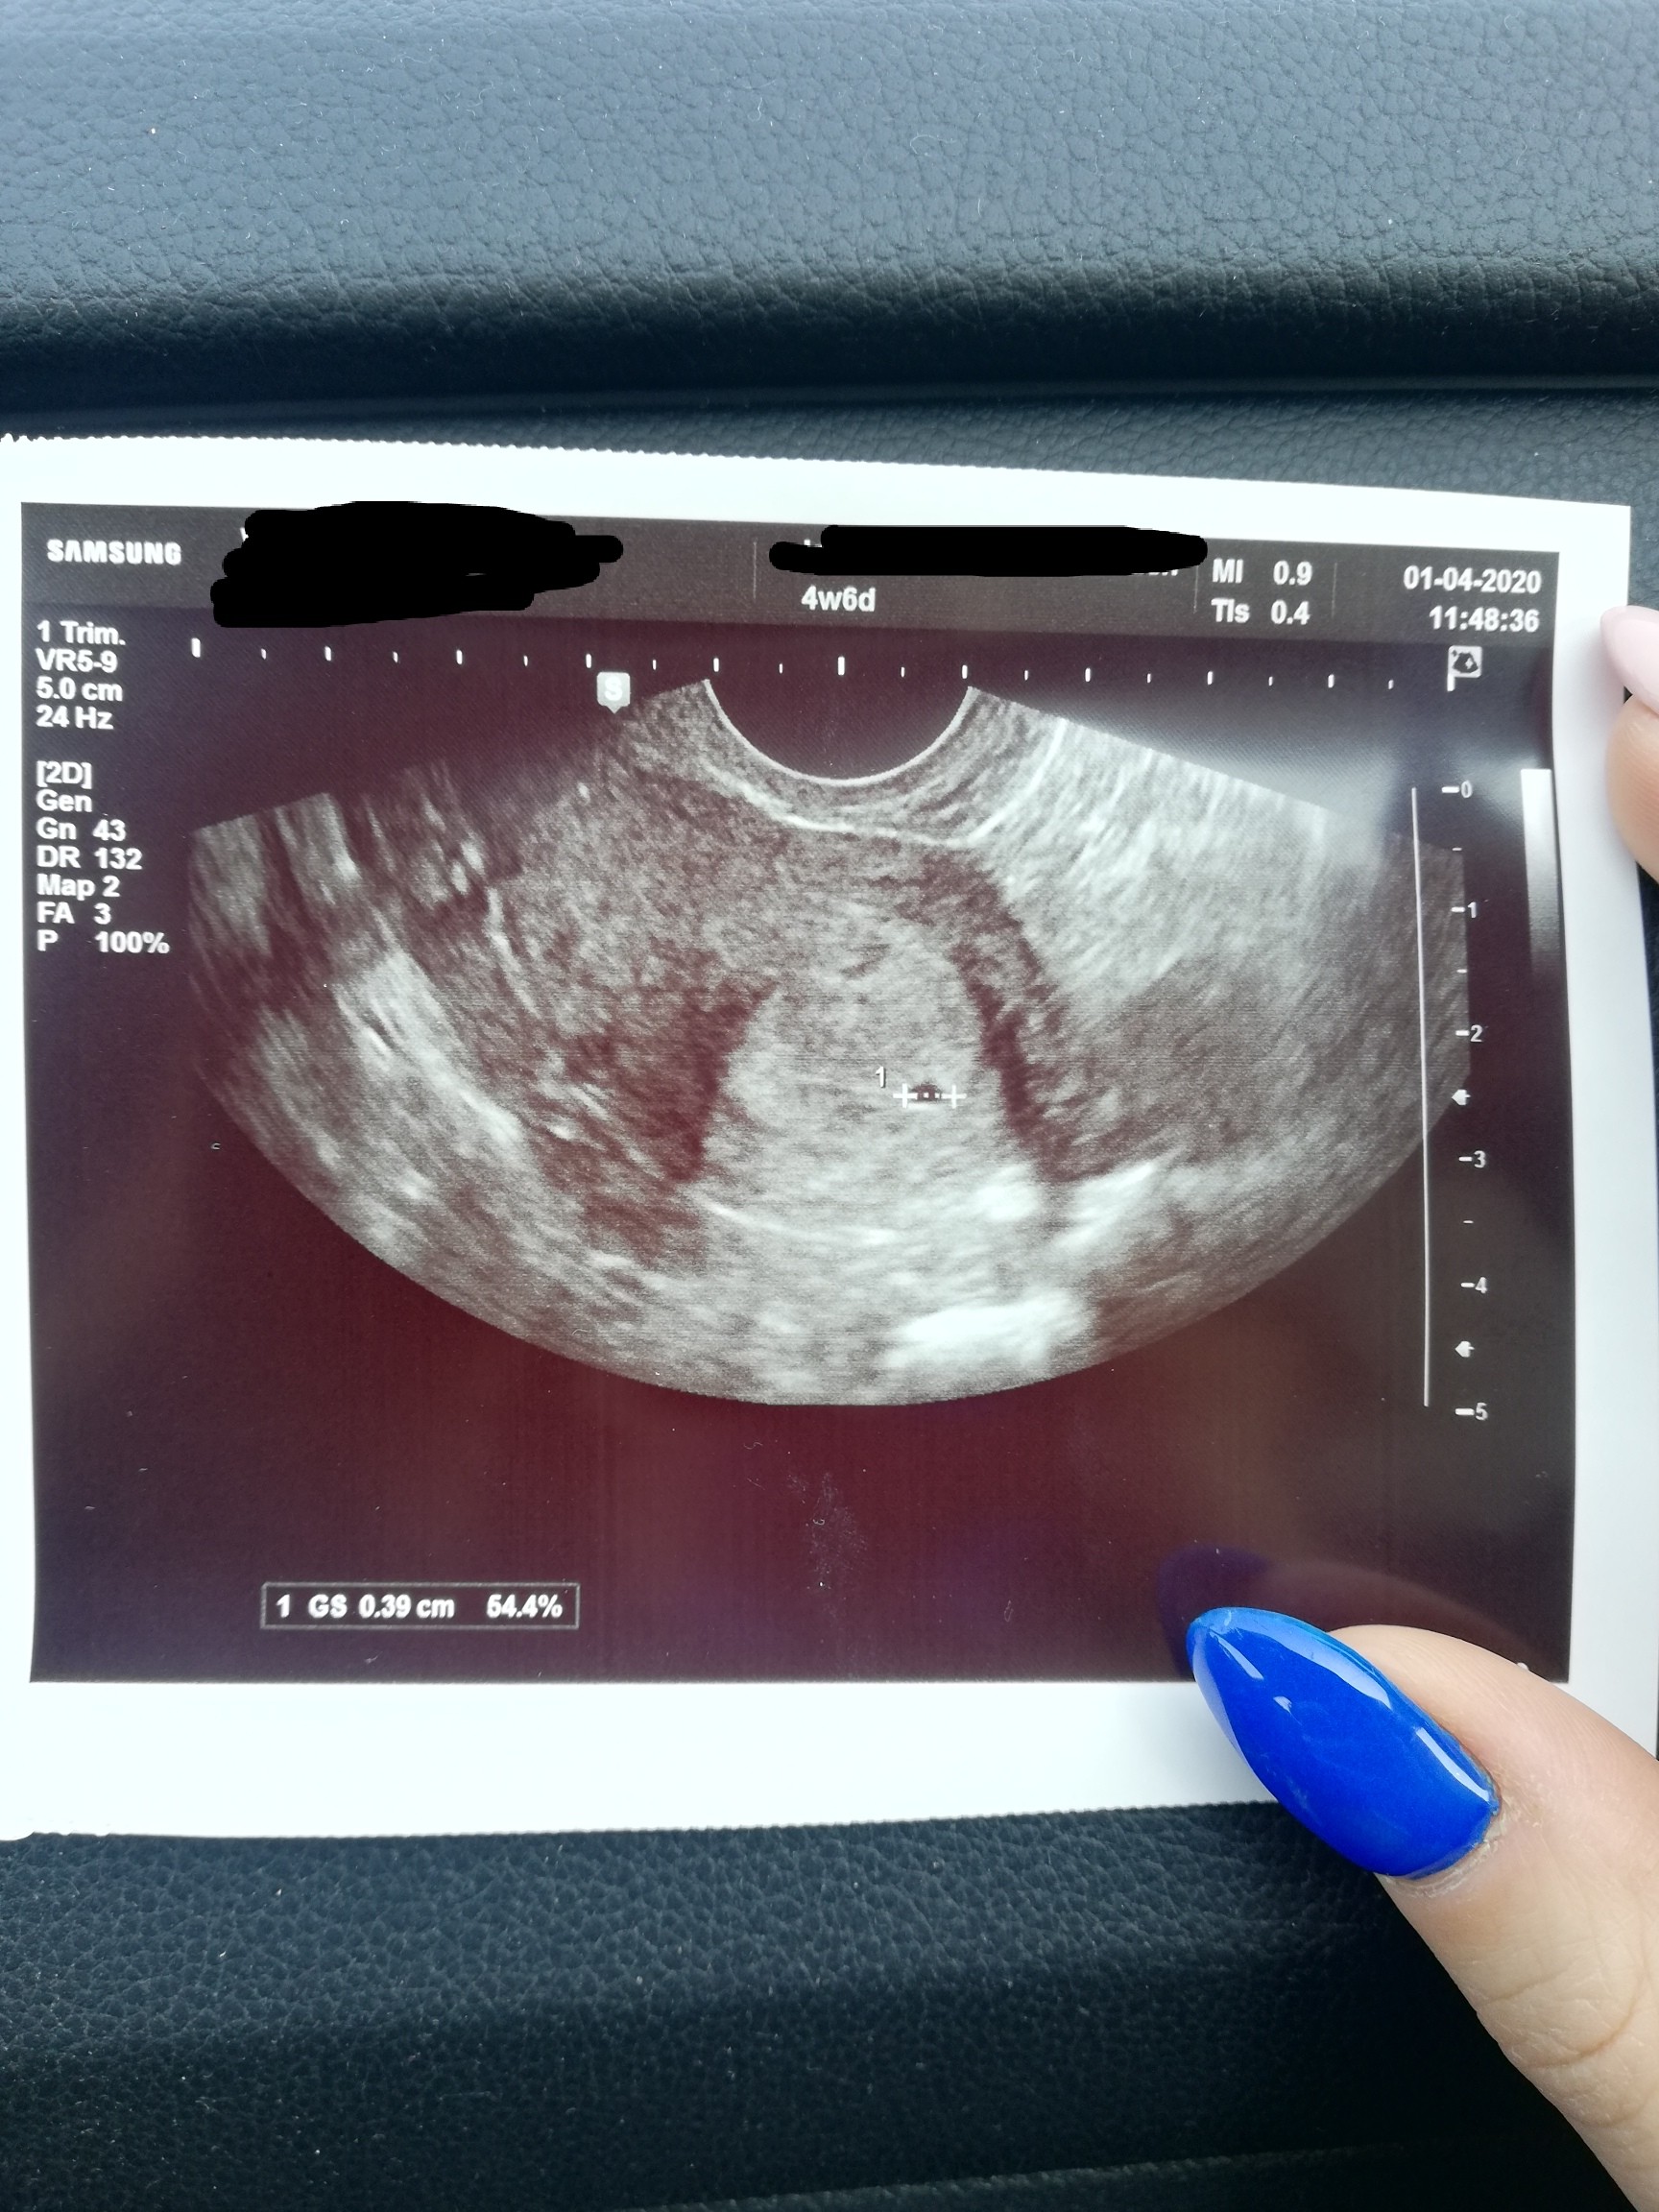

@młoda1994 gdzie to jest zaznaczone?

IMG_20200401_121641.jpg

Chyba to MI 0.9cm ale nie jestem pewna. Po prawej stronie u góry a pod tym MI jest ze pęcherzyk ciążowy miał 0.4cm czyli wychodzi na to że ze endometrium miałaś 9mm czyli trochę większe niż ja.

Tylko nie jestem pewna czy endometrium ciążowe jest opisane w mm czy cm. Lekarz mówił po niemiecku ale nie zrozumiałam jednostki ale jak bym miała 4+6 7.8cm to za duże endo jak na ten tydzień ciąży.